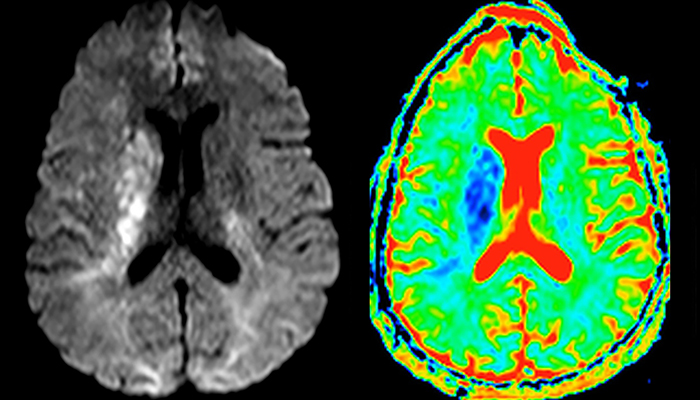

The first challenge in MRI of stroke is speed. The patient typically arrives from an ambulance in the MRI preparation room and the installation is done on a separate dock outside the scanner room. “The venous access is placed during the neurological examination. If the delay from the first symptoms allows the patient to receive thrombolysis we do a very fast examination that typically lasts about 11 minutes including the pre-scans. In the case of transient ischemic stroke we usually add ASL perfusion because in some symptoms with negative diffusion, ASL sometimes indicates a vascular origin.”

“Ingenia provides great flexibility in the parameters setting. We can tune a sequence the way we want,” says Dr. Savatovsky. “For example, in a stroke exam we use a FLAIR sequence of about two minutes instead of the four-minute FLAIR we use for MS. The diffusion is 30 seconds, the T2*-weighted scan is 30 seconds, the angiography scan time is less than one minute. Ingenia is a great scanner in that situation; even with these fast sequences we can achieve good images with good SNR. When the first sequence tells us that it’s not an ischemic stroke but a hemorrhagic stroke, we may switch to a time-resolved angiography to look for vascular malformations and venous thrombosis.

“Every center is different, but for me the ideal protocol for stroke includes diffusion weighted imaging, FLAIR, and fast susceptibility imaging,” says Dr. Savatovsky. “Our fast susceptibility weighted imaging takes 50 seconds, so it’s as fast as T2*-weighted imaging. It visualizes hemorrhage but also the clots. We also do 3D MR angiography that provides information on cervical and brain vessels. If the patient does not need immediate treatment, or if additional information is needed to decide on treatment, we might also add perfusion imaging and post-contrast T1-weighted imaging.”